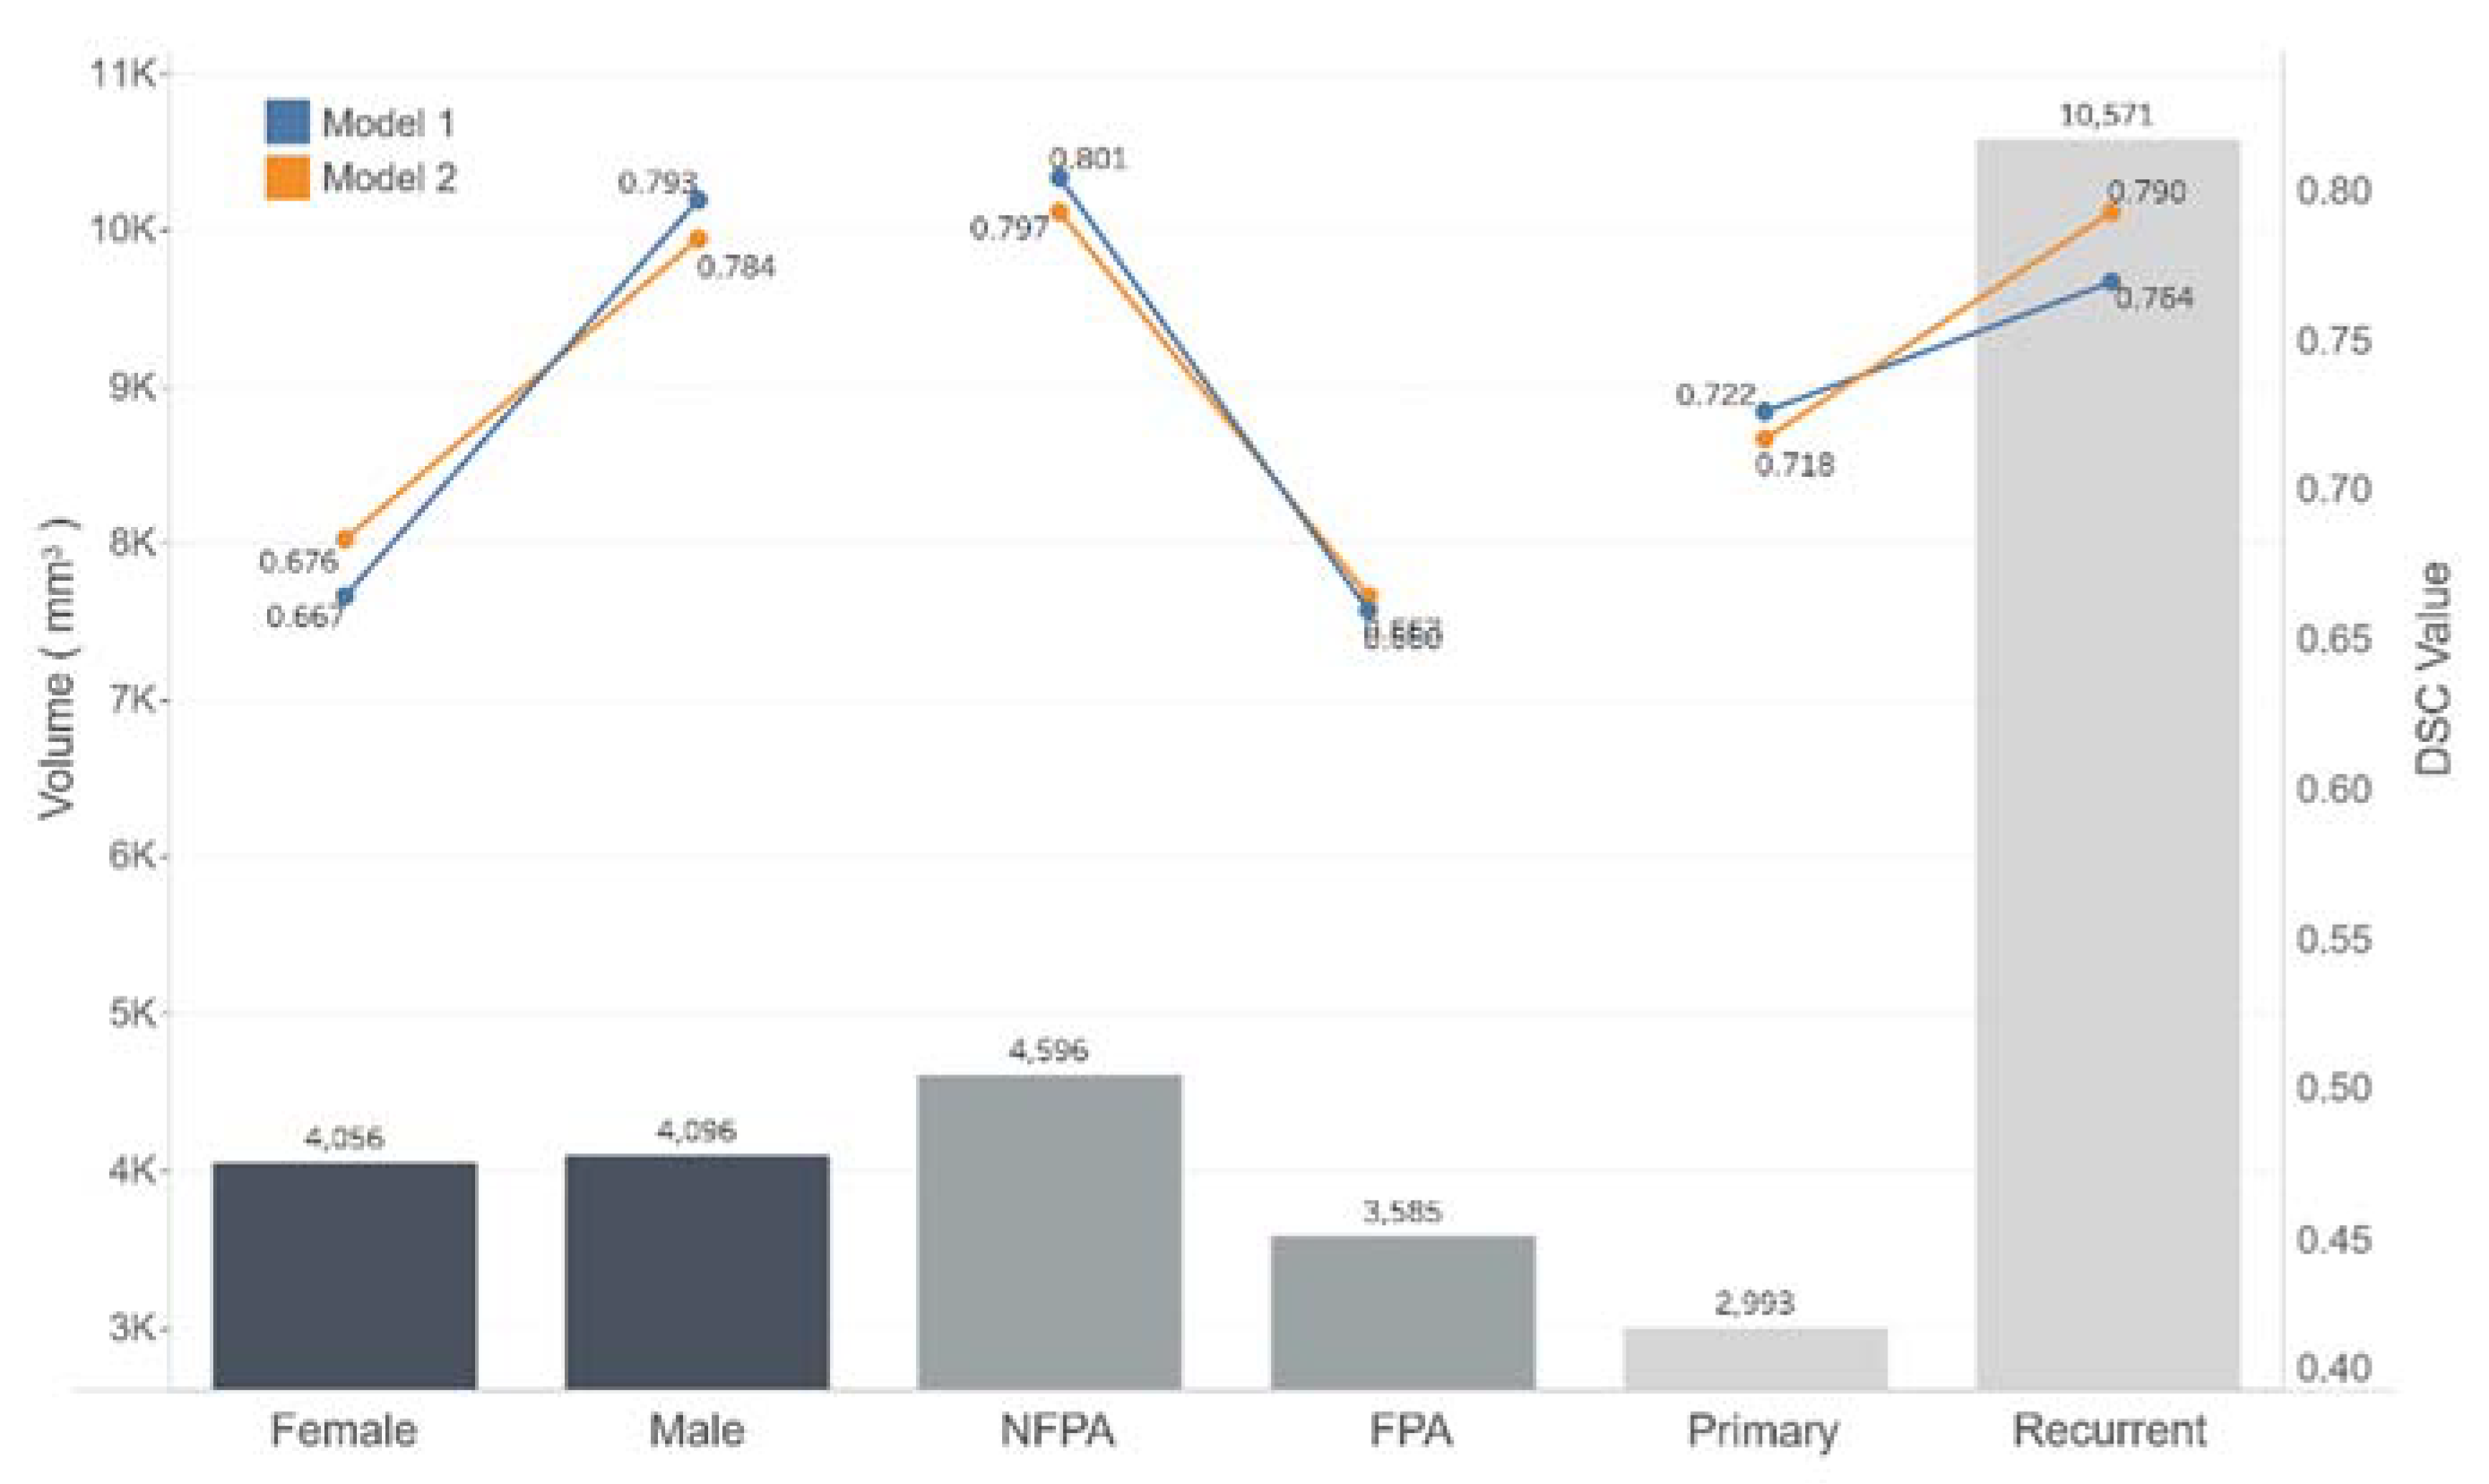

3.4. Model Performance in the Testing Dataset

3.5. Performance Comparison between the Two Models

3.6. The Relationship between DSC Values and PA Volumes